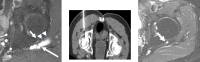

Objective: Acetabular paralabral cysts are common and are almost always associated with labral tears. Uncommonly, they extend into the periacetabular soft tissues or may propagate along peripheral nerves causing pain and hip dysfunction. The aim was to evaluate the clinical and MRI presentations of such cases including perineural propagation.

Results: 14 cases were recorded. The mean age was 56.9 years (range = 30-79 years) and female:male ratio was 1:2.6. The commonest presenting complaint was hip pain (10/14, 71.4%). Other complaints included groin pain, perineal pain and hip dysfunction. No symptoms were attributed to the acetabular paralabral cyst in 3/14 patients (21.4%). None had foot drop. The cysts were multilocular in all cases and were homogenously T2 hyperintense in 13/14 (92.9%). Labral tears were identified in 11/14 cases (78.6%). The sciatic nerve was most commonly involved in 5/14 cases (35.7%) with the obturator, medial femoral cutaneous nerve, femoral nerve, superior and inferior gluteal nerves also affected.No intervention was undertaken in 9/14 cases (64.3%). 5/14 (35.7%) underwent image guided aspiration and corticosteroid injection. 4/5 such patients reported reduced pain following the procedure.